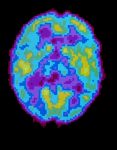

A PET scan of a brain during normal sleep. Two scientists say sleep may help the brain prune back unneeded synapses. Read More »